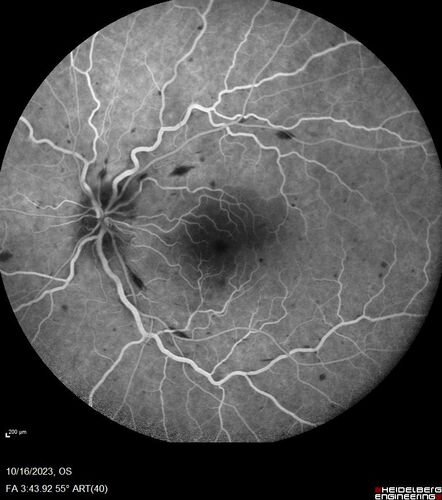

Central Retinal Vein Occlusion with cilioretinal artery occlusion

63 year old female who lost vision in the left eye 2 days ago. She was in the emergency room and had a lot of tests done which were all reportedly normal. The right eye is OK.

VA OD: Dcc20/25 NccJ2

VA OS: Dcc20/200-1 PHNI Ncc20/400-1

IOP: TP: OD:11 OS:12